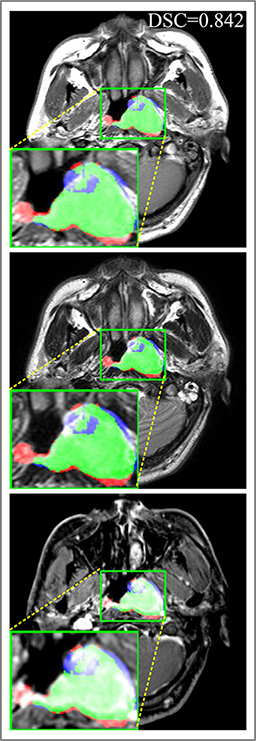

Comparison with ground truth. Some predicted results of MMFNet are shown in 2D images and 3D images in Figure 7 and Figure 8. As shown in these figures, although the shape and size of NPC are varied from each other, MMFNet can still accurately determine the regions of NPC and obtain the accurate contours of tumors. Through analyzing 2D images in figure 7, MMFNet has a capacity to fuse multi-modality MRI to reduce the confusion brought by intensity’ similarity between nearby tissues and NPC. The values of , and of MMFNet are shown in Table 1. MMFNet can reach the best results with , and .

Comparison with related works. Table 1 reports the values of , and for different methods. Predicted masks of different methods are illustrated in Figure 9 and Figure 10, which respectively present results in 2D and 3D images. Through comprehensively analyzing these results, the proposed MMFNet actually have the following properties:

Some typical predicted results of MMFNet are visualized in Figure 12. And it is worth mentioning that our proposed network is extremely time-friendly compared to manually marking by radiologists. Specifically speaking, our proposed method only needs about 9s to realize NPC delineation of a patient, while an experienced radiologist needs 10 to 20 minutes to complete it.